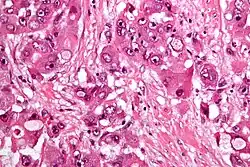

Micrograph of fibrolamellar hepatocarcinoma showing the characteristic laminated fibrosis between the tumor cells with a low NC ratio. H&E stain.

Fibrolamellar carcinoma (FLC) is a rare form of carcinoma that typically affects young adults and is characterized, under the microscope, by laminated fibrous layers interspersed between the tumor cells.[1] It has been estimated that 200 new cases are diagnosed worldwide each year.[2] However, in light of recent advances in our molecular understanding, this has recently been revised to suggest it may be at least ten times more common.[3] FLC, also known as fibrolamellar hepatocellular carcinoma, is different from the more common hepatocellular carcinoma (HCC) in that it afflicts young people with normal liver function and no known risk factors.[1][2][4][5]

The histopathology of FLC is characterized by laminated fibrous layers, interspersed between the tumor cells. Cytologically, the tumor cells have a low nuclear to cytoplasmic ratio with abundant eosinophilic cytoplasm.[1] Tumors are non-encapsulated, but well circumscribed, when compared to conventional HCC (which typically has an invasive border).